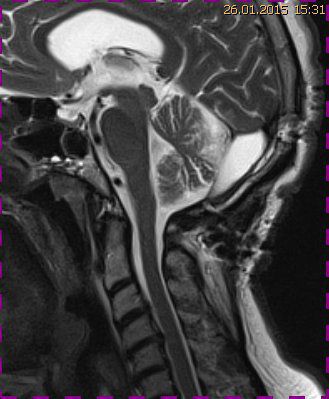

Abb. 1.2 Sagittales MRT (T2 TSE, 1 T): Streckfehlhaltung der HWS und oberen BWS, kein Frakturhinweis oder posttraumatische Myelopathie; die Kleinhirntonsillen reichen bis in das Foramen magnum

Das Fallbeispiel 1 zeigt im Verlauf eine Komplikation bei einer Arnold-Chiari-Malformation Typ 1 bei einem zum Zeitpunkt der Erstdiagnose 12-jährigen Jungen. Dieser hatte im Sportunterricht einen schweren Medizinball geköpft und ein Stauchungs-trauma der Halswirbelsäule erlitten. Nach anfänglich symptomatischer frustraner Therapie wurde er vom behandelnden Orthopäden zur MRT der HWS überwiesen. Es wurde eine Streckfehlhaltung und flachbogig rechtskonvexe Skoliose diagnostiziert, klinisch bestand ein Torticollis. Eine knöcherne oder ligamentäre Verletzung wie auch eine Schädigung des Rückenmarks bzw. eine intraspinale Bandscheibendislokation konnten bildmorphologisch ausgeschlossen werden.

Trotz weiterer Schmerz- und Physiotherapie konnte keine Beschwerdereduktion erreicht werden. 2 Monate später erfolgte eine MRT des Kopfes zum Ausschluss einer posttraumatischen Veränderung.

Bei dieser Untersuchung wurde übersehen, dass die Kleinhirntonsillen in das Foramen magnum disloziert waren und eine Arnold-Chiari-Malformation mit Erweiterung des 4. Ventrikels und des Aquäduktes inklusive Kleinhirntonsillentiefstand vorlag. Bei zwischenzeitlich auswärtig erfolgtem CT der HWS wurde eine Anlagestörung im kraniozervikalen Übergang beschrieben. Eine Kontrolluntersuchung des Kopfes weitere 4 Monate später dokumentierte neben einem medullären Ödem einen progredienten Tonsillentiefstand, der zur neurochirurgischen Behandlung mit operativer Erweiterung des Foramen magnum führte.